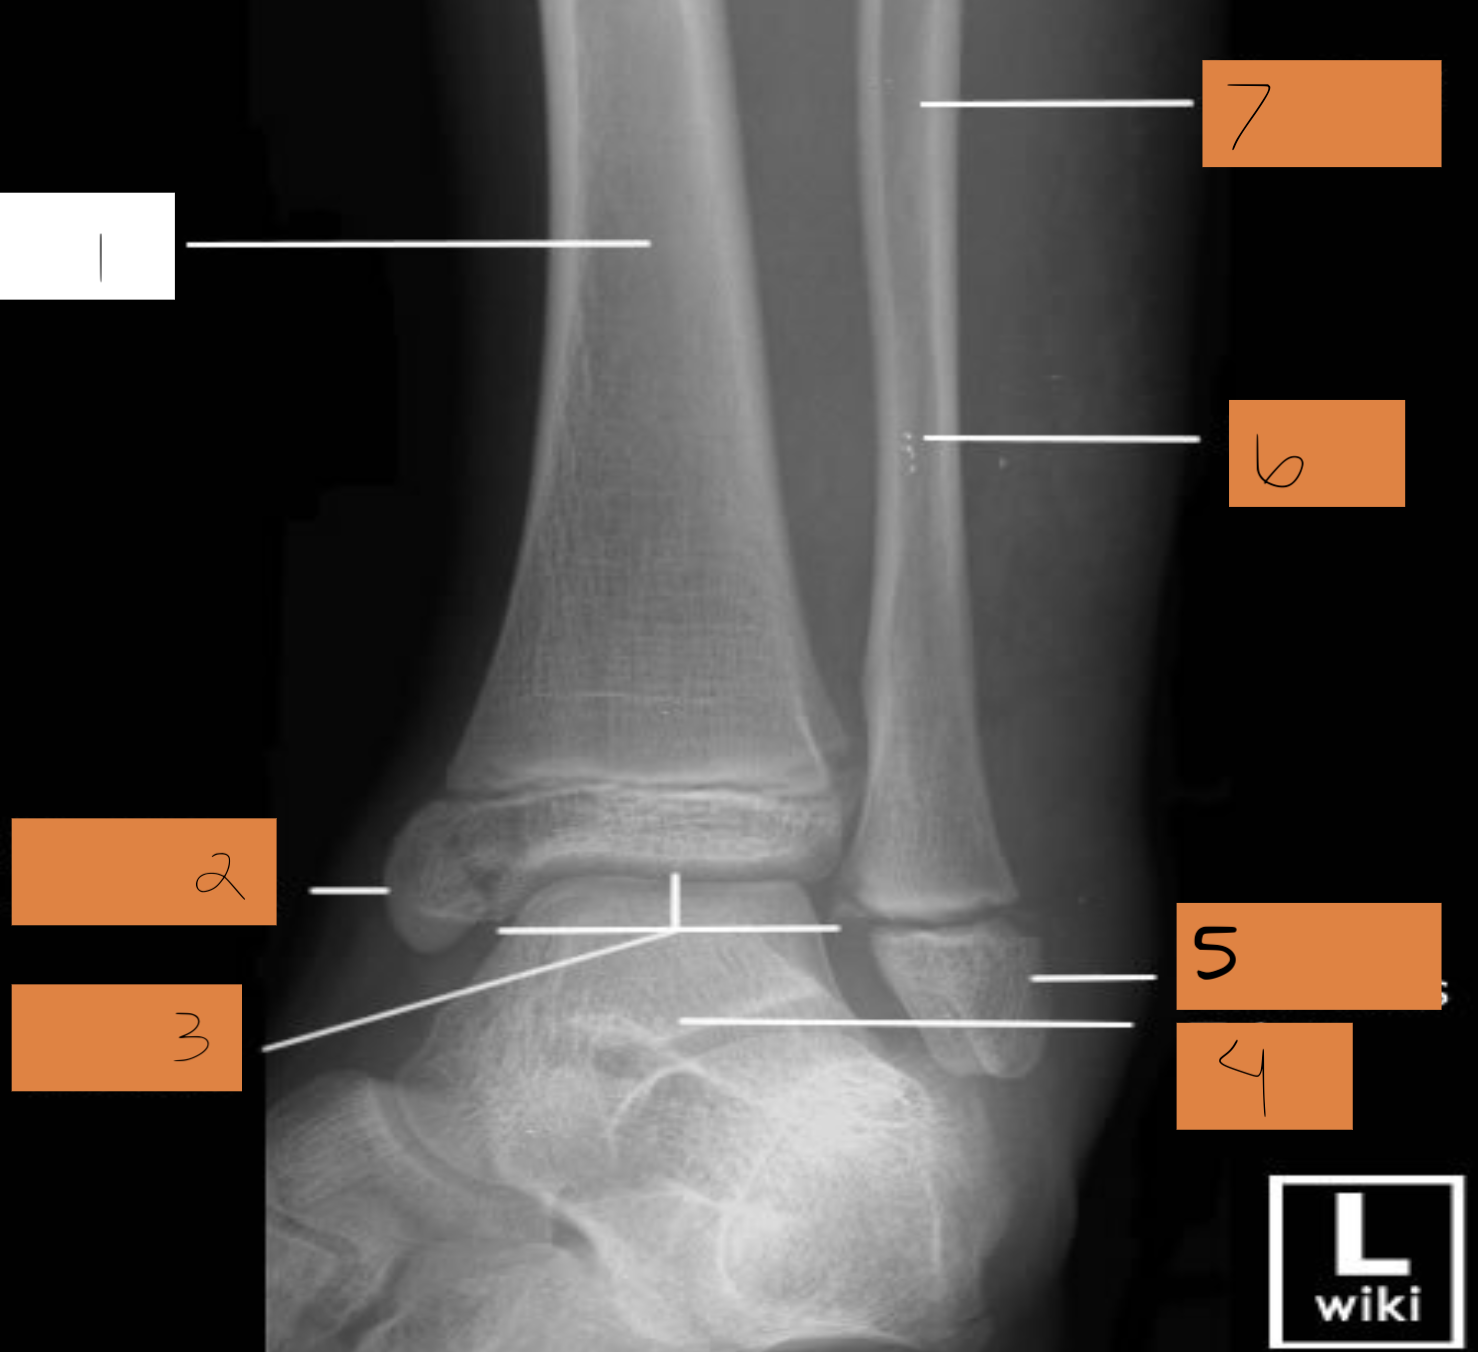

1

tibia

2

tibiotalar joint

3

tarsals

4

metatarsals

5

phalanges

6

sesamoid bones

7

navicular

8

sinus tarsi

9

calcaneum

10

fibula